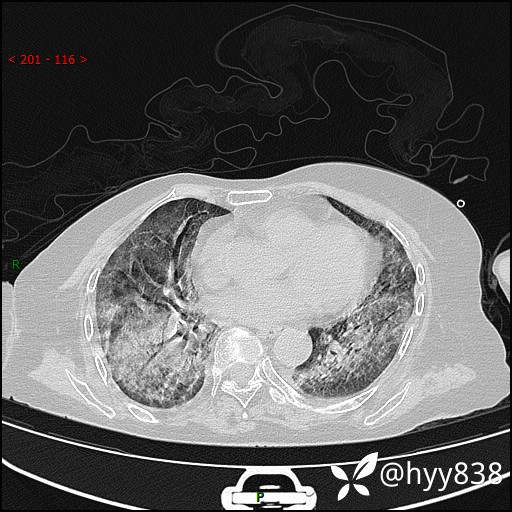

弥漫性肺部病变,辗转当地多家医院未能确诊,拟诊“重症肺炎”入我院--结果公布

患者年龄:69岁

简要病史: 患者20余天前无明显诱因出现发热,最高体温37.5℃,伴头晕,乏力,纳差等不适,无鼻塞,流涕,无咳嗽咳痰,无呼吸困难,无恶心呕吐、关节疼痛等不适,于当地市多家医院就诊,未明确病因,2023.6.23于当地第二人民医院就诊,完善胸部CT示病毒性肺炎,予以抗感染、清热解毒后症状较前稍好转,2天前患者无明显诱因出现活动后喘息加重,伴肌肉酸痛,口干,无明显咳嗽咳痰,今日体温38.1℃,为求进一步诊治来我院就诊,门诊以“ 重症肺炎 I型呼吸衰竭”收入院。 患者起病以来,精神、睡眠、饮食欠佳,大小便正常,体力下降,体重无明显改变。

辅助检查:CT

临床诊断:重症肺炎

胸部CT薄层扫描